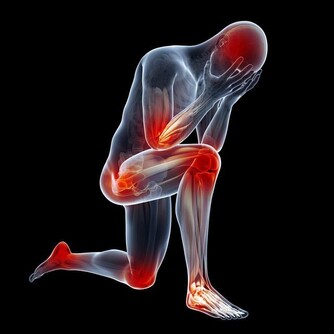

我們知道膝蓋是我身體的一個重要的組成部分,

只有擁有一個健全的完好的膝蓋我們才能夠讓自己活的更加的年輕,

在平時的生活中才能夠步伐更加的強勁有力。

在美國,每年有高達900多萬人去骨科就診,其中大部分都是出於膝蓋的不適。

但不用擔心,如果能稍加註意的話,大多數人根本就不用去醫院。